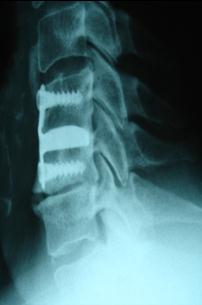

The X-ray appearance 7 years later. The fusion is solid.